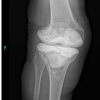

Immediately following the Stage 2 procedure, the patient was started on intravenous (IV) antibiotics. He received IV daptomycin 700 mg/24 h and piperacillin/tazobactam 3.375 g/6 h for a total duration of 5 weeks post-reimplantation. Following the completion of the IV antibiotic course, the patient was transitioned to oral doxycycline 100 mg twice daily. This oral antibiotic regimen was planned to continue for 3 months, extending the total duration of antibiotic treatment to approximately 4.5 months post-reimplantation. 1 month after the stage 2 procedure, the surgical incision was noted to be dry and well-healed. X-rays taken at this time showed that the implants were well-aligned and well-fixed, with no evidence of loosening or osteolysis. The patella was also well-positioned. The range of motion was noted to be from 0° of extension to 110° of flexion. He reported no pain at this visit. 1 year after the stage 2 procedure, repeat X-rays were obtained. These images again demonstrated that the implants remained well-aligned and well-fixed. There was no evidence of loosening, osteolysis, or any other signs of failure or recurrent infection (Fig. 8).